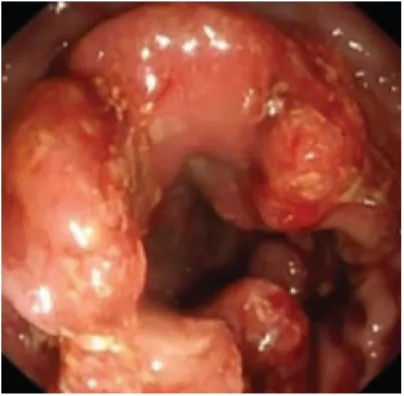

52세 여성이 3개월 전부터 경험한 좌하복부 통증과 4일 전 시작된 배변 시 출혈로 내원하였다. 대장내시경을 시행한 결과 아래와 같은 사진이 나왔다. 이 환자의 병변의 침윤 깊이와 진행 정도를 평가하기 위해 가장 먼저 시행해야 할 검사는?

• 좌하복부 불편감과 배변 시 출혈을 호소하는 환자이다. 대장 내시경에서 mass가 뚜렷이 관찰되어 대장암이 의심된다.

• 대장암의 확진을 위해 조직검사가 필요하며, 병기 평가를 위해 복부 CT를 시행하여 주변부 침윤 정도를 확인해야 한다.